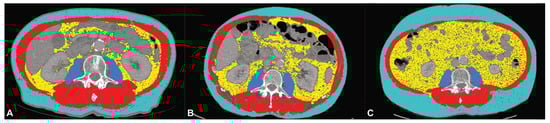

2.3. CT Body Composition Analysis

2.4. Statistical Analysis